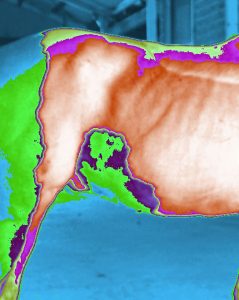

the dog had tumour

the dog had tumour  six weeks later after treatment it’s total free from tumour.

six weeks later after treatment it’s total free from tumour.

ERIC can detect injuries and sickness with horses.

Pictures show these horses have different body injuries and sickness.

Pictures show these horses have different body injuries and sickness.